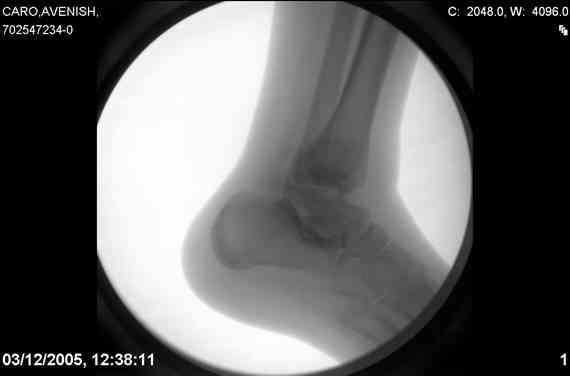

ya by popytalsya sobrat talus anatomichno,seichas pozdno operirovat

iz za oteka,po etomy distrakziya apparatom budet optmalna.Posyalu vam

podobyai moi sluchai.